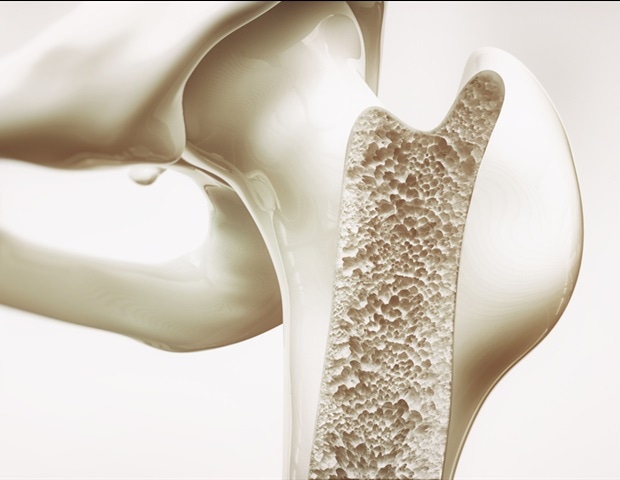

חוקרים מאוניברסיטת סוונסי פיתחו תחליף השתלת עצם מהפכני בהשראת אלמוגים אשר לא רק מקדם ריפוי מהיר יותר אלא מתמוסס באופן